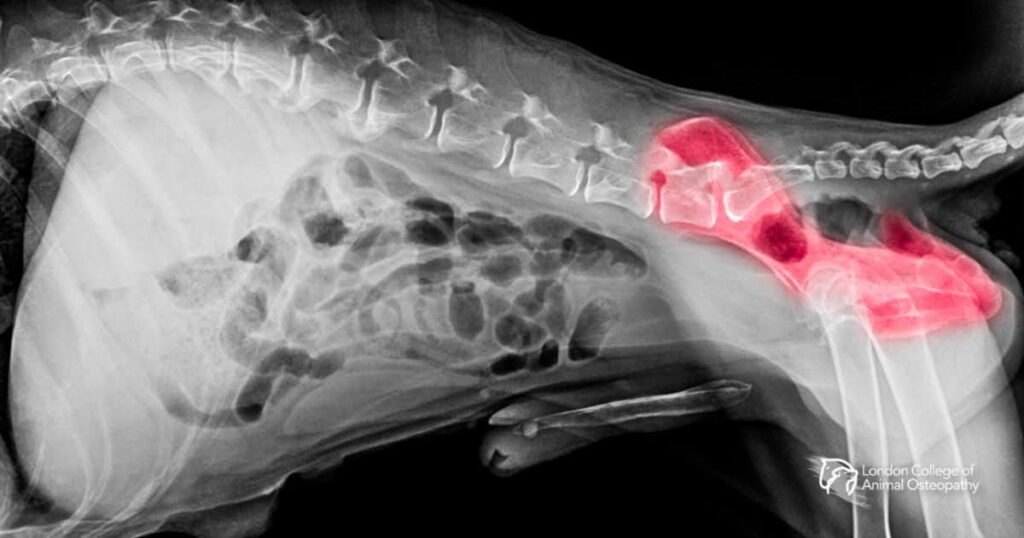

Understanding Hip Dysplasia in Dogs Hip dysplasia in dogs (often called CHD, or canine hip dysplasia) is a developmental joint condition in which the femoral head and the acetabulum don’t form a stable, congruent ball-and-socket joint. Over time, that laxity causes abnormal wear, inflammation, and osteoarthritis. Clinical signs range from subtle exercise intolerance to obvious lameness. […]